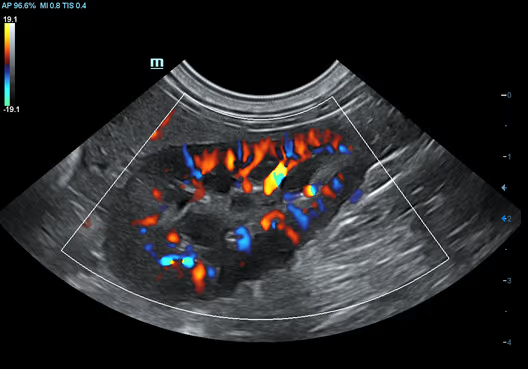

Köpek Kalbinin M Modu Rengi

Köpek Kalbinin M Modu Rengi